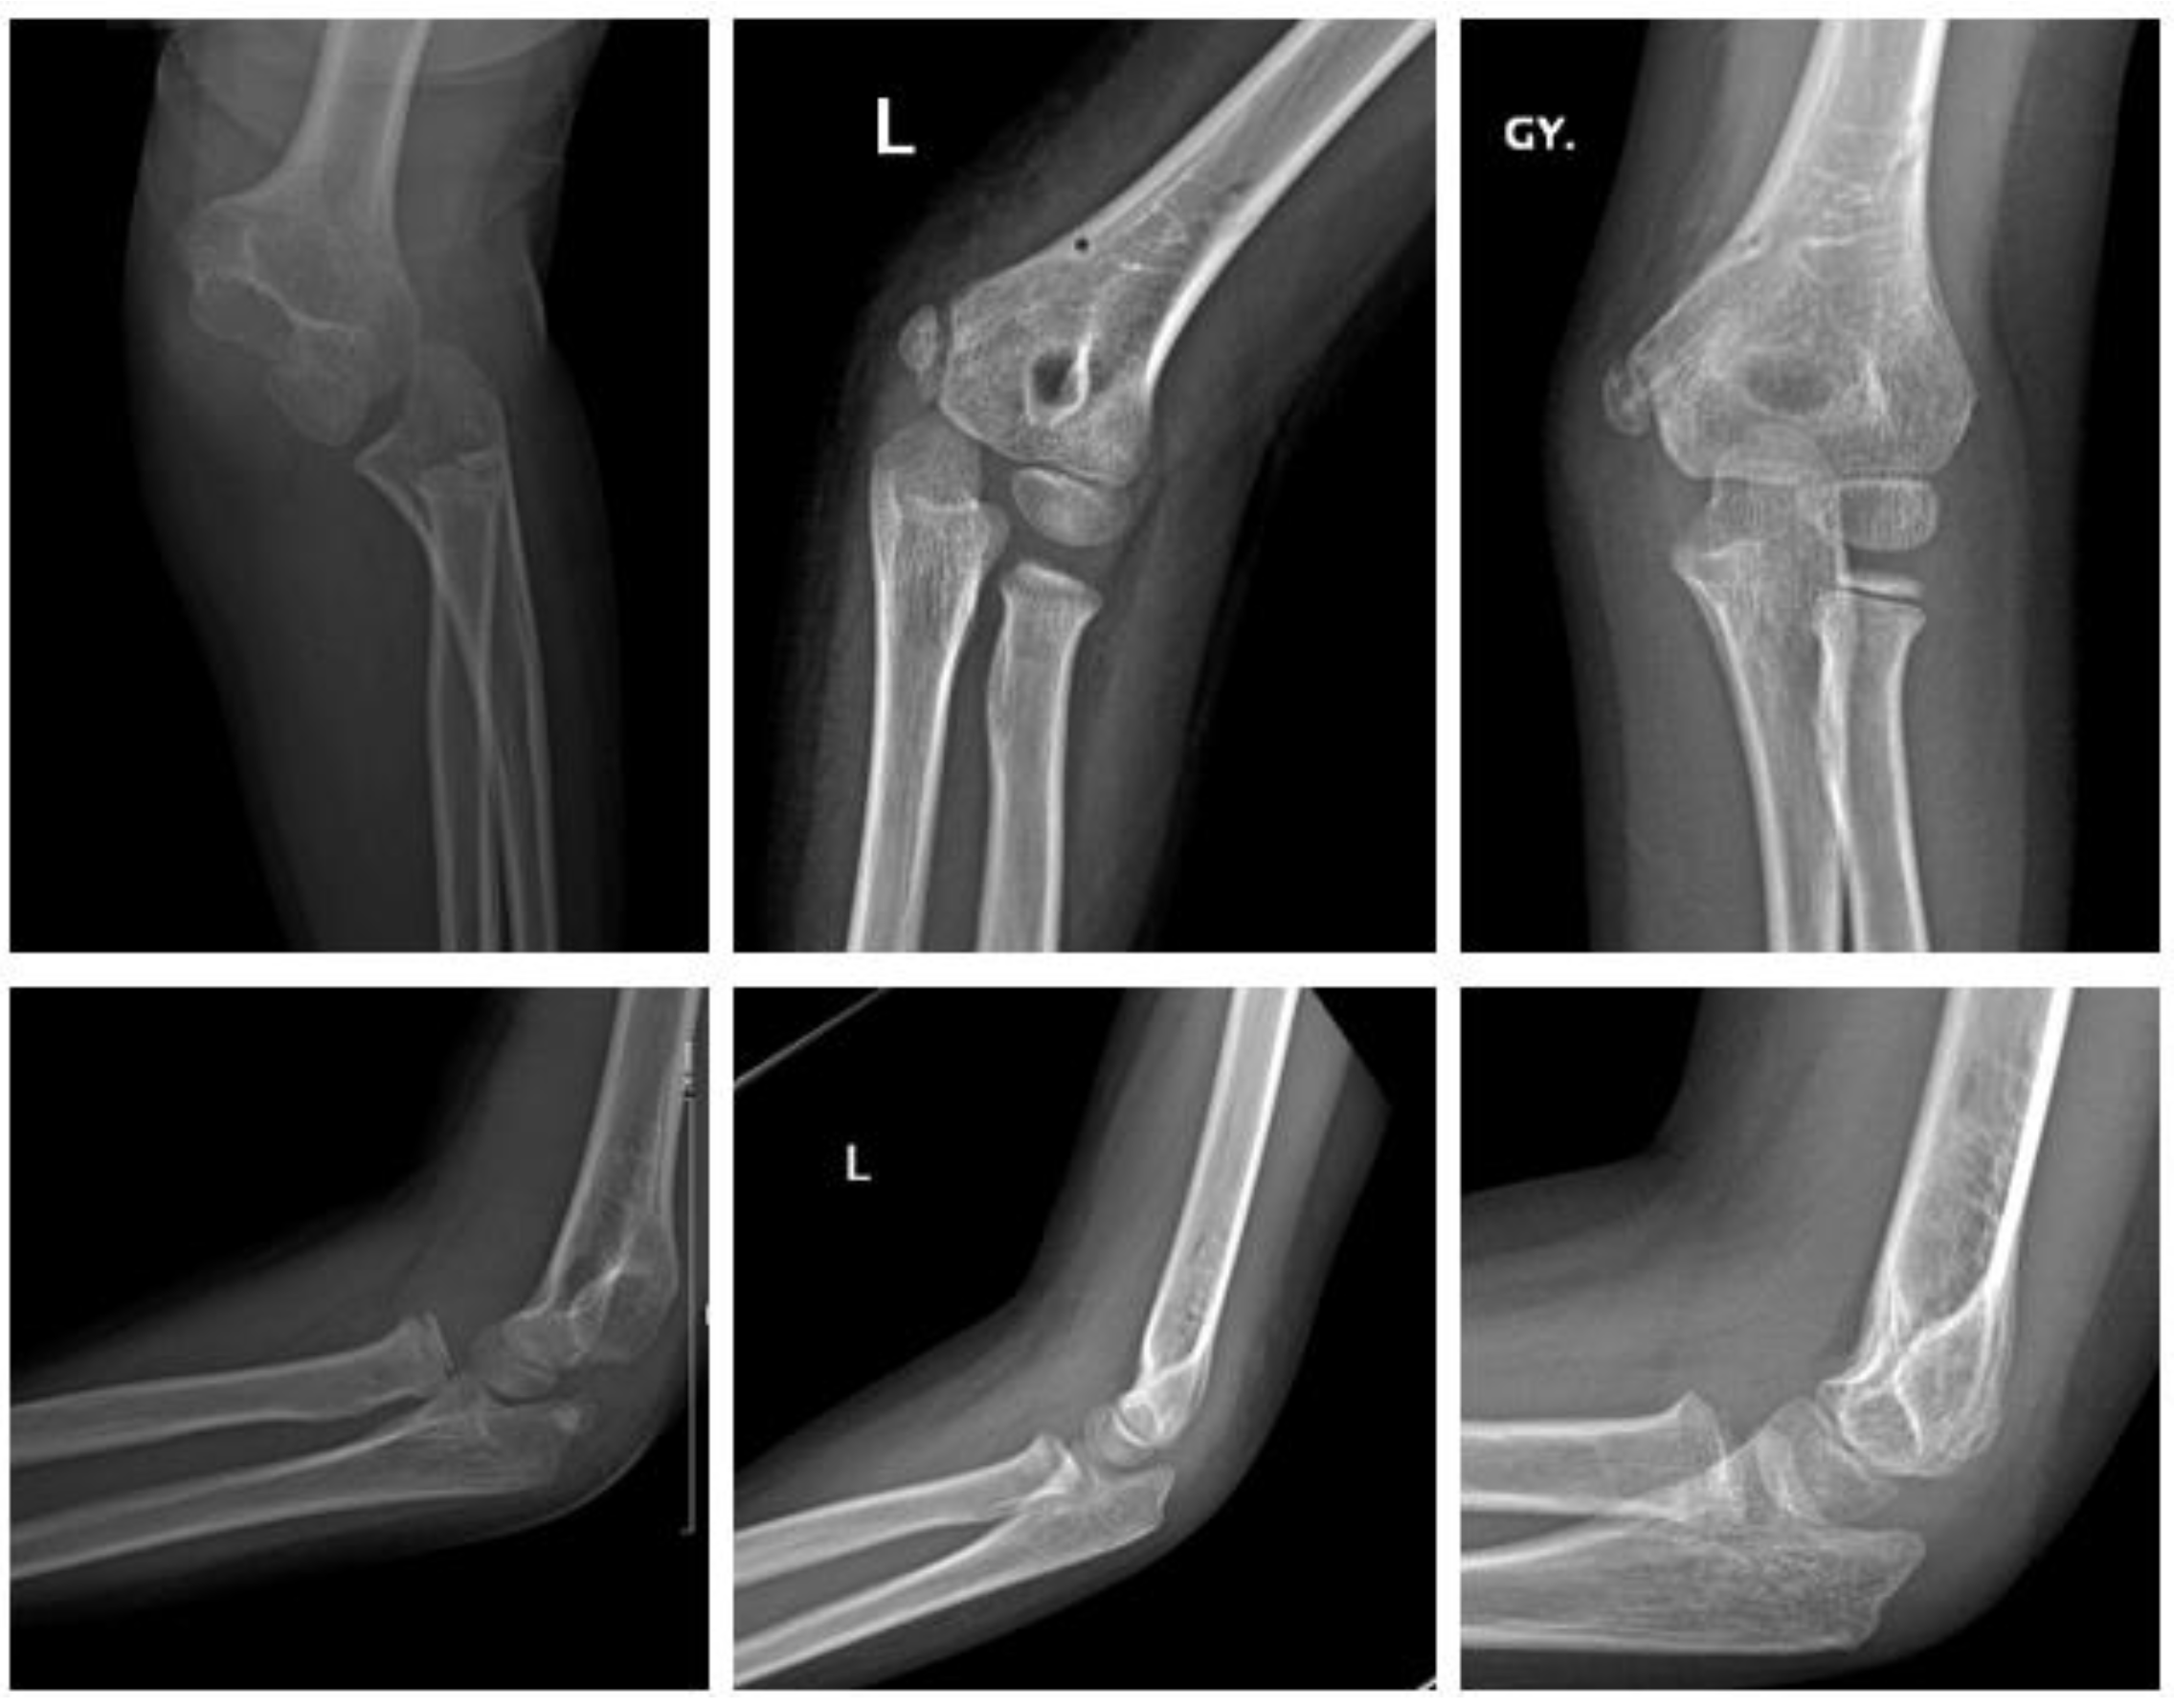

2.4.3. Fracture of the Lateral Condyle